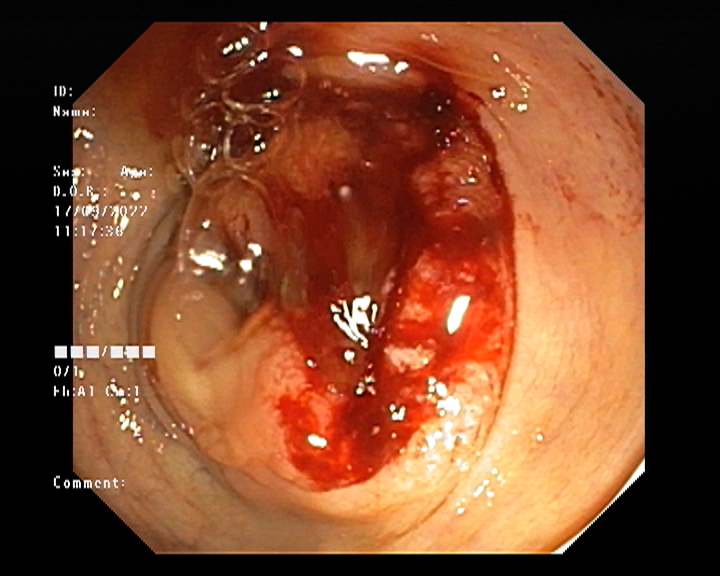

Endoscopy and colonoscopy are safe and accurate procedures used to directly examine the digestive tract and detect the root cause of chronic acidity, GERD, abdominal pain, bleeding, and bowel irregularities. These minimally invasive tests help identify ulcers, inflammation, infections, polyps, strictures, and early cancerous changes.

At Sapphire Gastroenterology Center, modern endoscopic equipment ensures precise diagnosis and, when required, therapeutic intervention during the same procedure. Based on findings, targeted treatment plans are created, including medication, diet guidance, and preventive strategies. Early diagnosis through endoscopy and colonoscopy plays a crucial role in preventing serious complications and improving long-term digestive health.